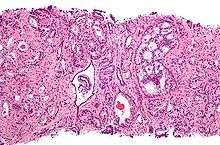

Micrograph showing a prostate cancer (conventional adenocarcinoma) with perineural invasion. H&E stain.

If cancer is suspected, a biopsy is offered expediently. During a biopsy a urologist or radiologist obtains tissue samples from the prostate via the rectum. A biopsy gun inserts and removes special hollow-core needles (usually three to six on each side of the prostate) in less than a second. Prostate biopsies are routinely done on an outpatient basis and rarely require hospitalization. Antibiotics should be used to prevent complications like fever, urinary tract infections, and sepsis.[75] Fifty-five percent of men report discomfort during prostate biopsy.[76]

The tissue samples are then examined under a microscope to determine whether cancer cells are present, and to evaluate the microscopic features (or Gleason score) of any cancer found. Prostate specific membrane antigen is a transmembrane carboxypeptidase and exhibits folate hydrolase activity.[77] This protein is overexpressed in prostate cancer tissues and is associated with a higher Gleason score.[77]